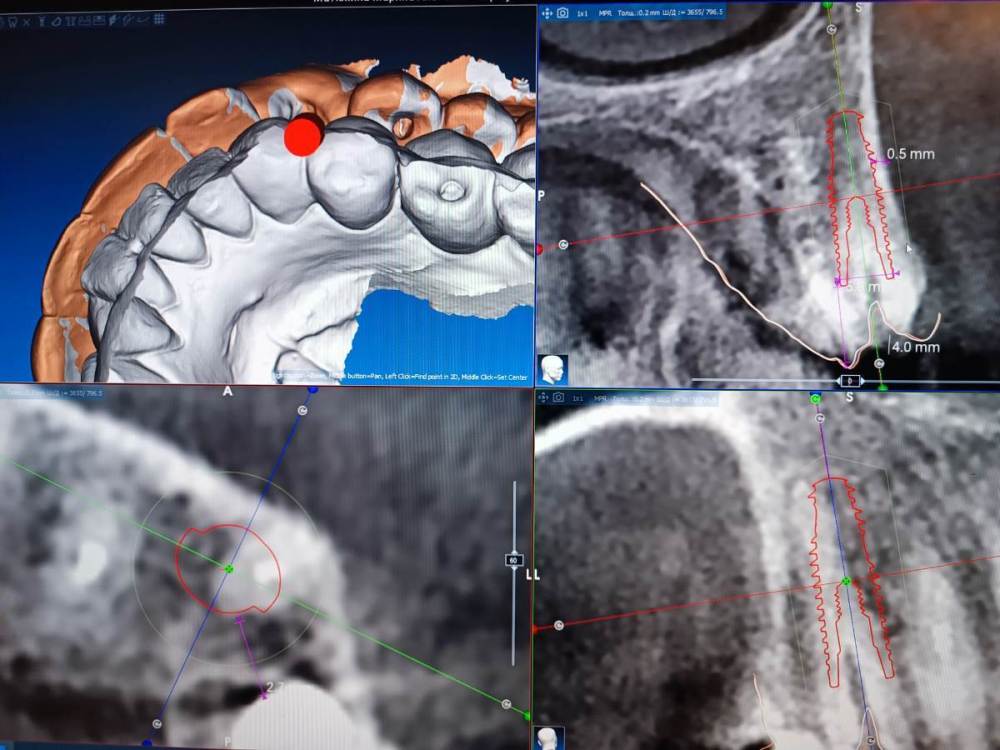

Fin Опубликовано 2 января, 2024 Поделиться Опубликовано 2 января, 2024 Коллеги всех с новым годом ?. Как считаете какое расстояние сейчас актуально между двумя имплантами?На данный момент есть установленная 4 ка но пациенту планируется одномоментная имплантация клыка.Сейчас по примерке расстояние получается 2 мм. Как бы Вы поступили в данном случае? Ссылка на комментарий

АнтонТЛТ Опубликовано 2 января, 2024 Поделиться Опубликовано 2 января, 2024 А если в лунку сместить? Ссылка на комментарий

Fin Опубликовано 2 января, 2024 Поделиться Опубликовано 2 января, 2024 2 часа назад, АнтонТЛТ сказал: А если в лунку сместить? Имеете ввиду вестибулярно? Ссылка на комментарий

АнтонТЛТ Опубликовано 2 января, 2024 Поделиться Опубликовано 2 января, 2024 Да, расстояние может получше будет? Ссылка на комментарий

Fin Опубликовано 3 января, 2024 Поделиться Опубликовано 3 января, 2024 18 часов назад, АнтонТЛТ сказал: Да, расстояние может получше будет? Да становится немного лучше но создает новую проблему одномоментной имплантации.Как вариант взять неодент 3.75, но не знаю выдержит ли. Ссылка на комментарий